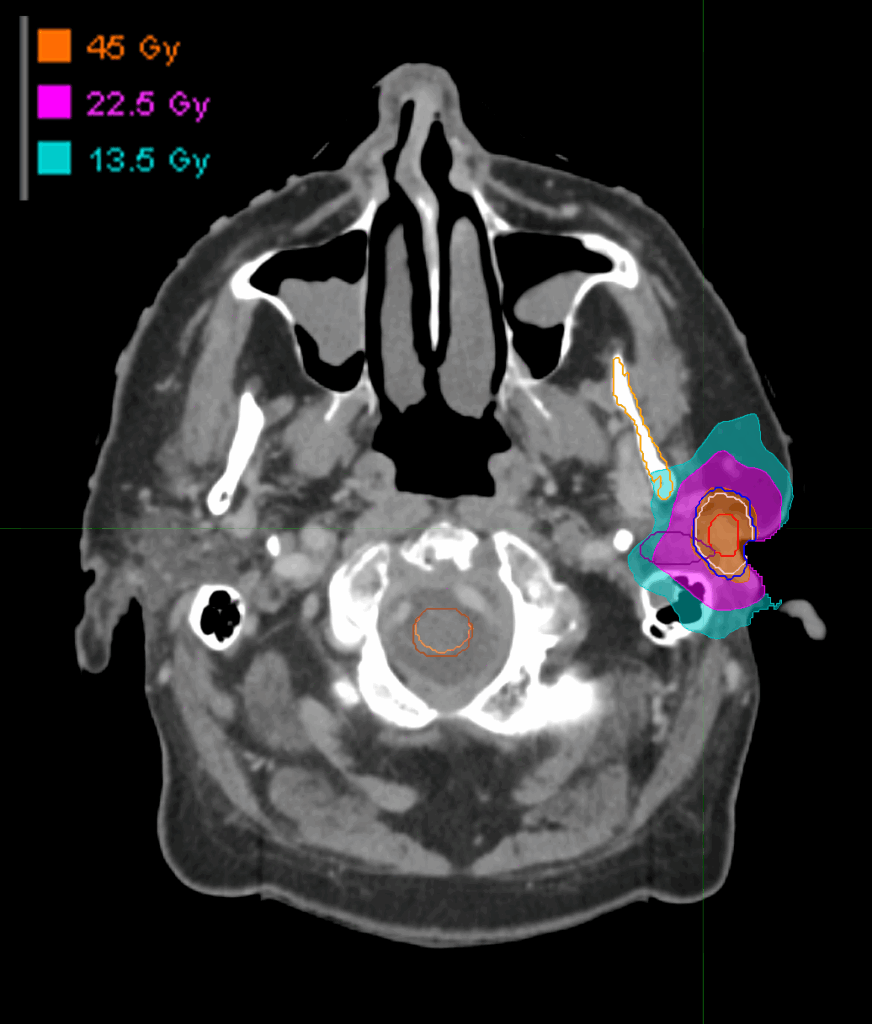

Treatment Plan Images

Dose Distributions

- Prescription to the

83% isodose line - Max. dose 54.35 Gy